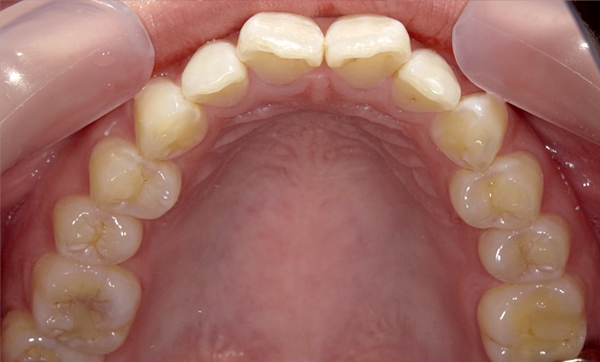

症例_008 「上下の前歯」症例

治療期間:13ヶ月金額:57万円+税40代女性捻転歯前歯のガタガタ

Before | After |